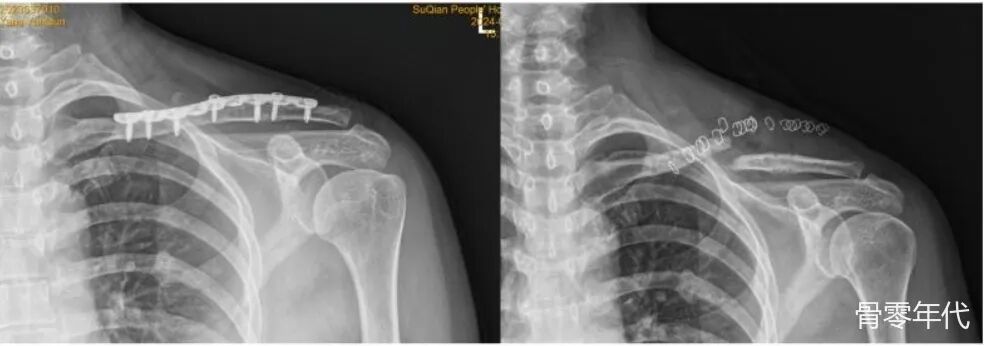

患者,女,47岁,她因骑自行车时摔倒导致左锁骨中段骨折,被归类为AO/OTA13B型,接受了“切开复位和锁板内固定”,术后17个月,患者来到我院要求拆除内固定。术前X线片显示骨折完全愈合,因此进行了锁骨内固定的移除。手术顺利,手术过程中未发现明显异常。术后第5天,患者主诉锁骨区域明显疼痛,没有任何外力,复查X线片显示锁骨骨折,在螺钉固定所在的位置。患者家属依从性强,与患者及家属深入沟通后,同意再次接受手术。手术中,清洗骨折末端后,再次进行锁板内固定,并进行自体髂骨移植。

术前X线检查提示左锁骨中段骨折,移位明显。术后X线:显示内固定到位,骨折对位良好。术后4个月X线片:骨折线仍清晰可见,提示骨折愈合延迟。术后11个月X光片:骨折线仍然清晰可见,这可能表明骨折尚未完全愈合或愈合过程停滞。术后17个月X光片:未见明显骨折线,通常表示骨折已愈合。拆除内固定后:骨折端移位,这意味着发生了骨折。切开复位和骨移植内固定后的X射线。

骨折愈合和拆除内固定后再骨折是一种罕见的并发症,偶尔见于锁骨、前臂和股骨等长骨。骨折发生一般无明显剧烈因素,以损伤部位突然剧烈疼痛为特征,通常需要再次手术进行内固定和骨折末端植骨,往往效果良好。此前有研究报道,锁骨中段骨折拆除内固定后,折骨折位多在原骨折部位,一小部分发生在用于固定骨碎片的螺钉孔处。在这项研究中,折射的位置在皮质螺钉孔处。至于钢板移除和再骨折的间隔时间,不同研究报道的间隔时间各不相同,Tsai等报告平均为23.9 d,Zhu等报告了25.6 d。本报告中的患者与上述研究不同,因为骨折发生在住院期间,间隔时间仅为5天。锁骨中段骨折拆除内固定后折骨折的相关因素包括:1.骨折的粉碎程度、复位质量、分类。在ZHU等的研究中,2B2型患者的骨折率是2A型的7.9倍,复位不良患者的折断率是复位良好的患者的15.8倍,性别和BMI,BMI低的女性发病率较高。